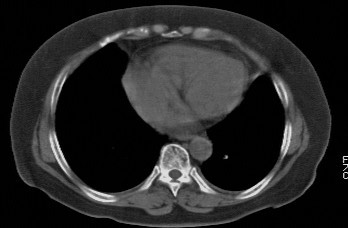

f,74发热咳嗽三天

考虑左肺上叶中央型肺癌并左肺上叶舌段肺不张。

考虑左肺上叶中央型肺癌并左肺上叶舌段肺不张.

左肺上叶舌段肺不张,建议作进一步检查除外中心型肺癌。

左肺上叶舌段肺不张,建议行纤支检查除外中心型肺癌。支持!